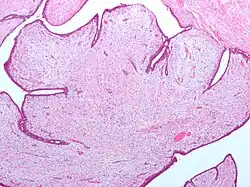

Fibroepithelial neoplasm (Phyllodes tumor).

A fibroepithelial neoplasm (or tumor) is a biphasic tumor. They consist of epithelial tissue, and stromal or mesenchymal tissue. They may be benign or malignant.[1]